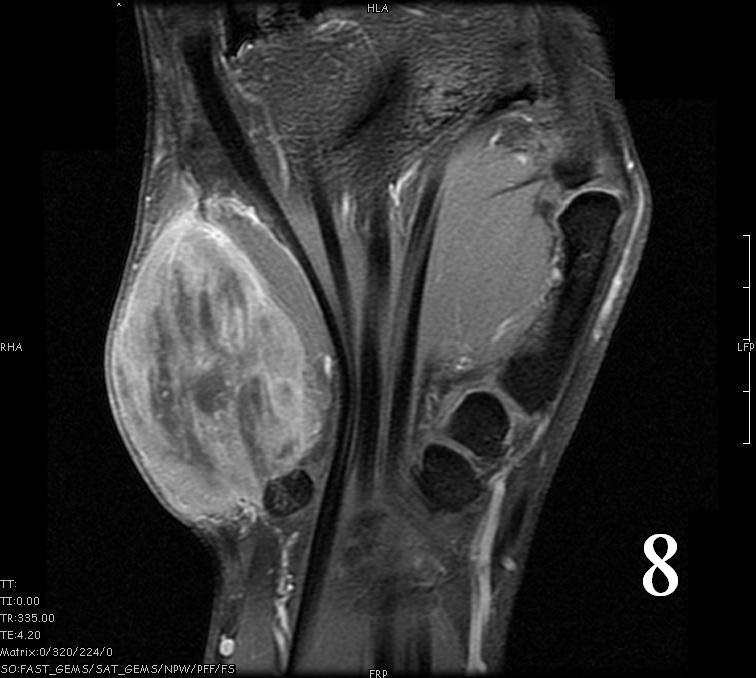

- Isointense to skeletal muscle on T1 (Fig. 4, Fig. 5, Fig. 7, Fig. 8)

- Hyperintense signal on T2, sometimes low to intermediate signal on T2 if there is extensive fibrous tissue within the tumor (Fig. 6, Fig. 9).

Fig. 4-9: MRI of a rhabdomyosarcoma of the hand. The MRI is nonspecific and shows a heterogeneous mass particularly on postgadolinium images T1 W images (Fig. 8) and T2 W images (Fig. 9).